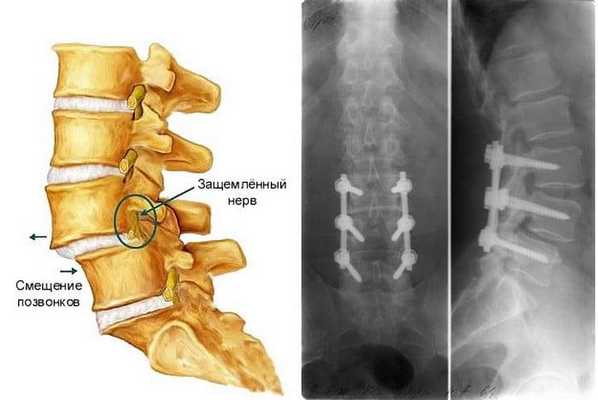

Операция при смещении позвонков

Нельзя оставлять без внимания болевой синдром, который локализируется в любой части позвоночного столба, так как он может свидетельствовать о развитии серьезной проблемы - смещении позвонков, или, как его называют по-научному, спондилолистезе. Заболевание, которое развилось в поясничном отделе, крайне опасно своими осложнениями. При отсутствии своевременного лечения могут произойти критические изменения в работе органов малого таза, потеря чувствительности и двигательного потенциала нижних конечностей, что в свою очередь способно обречь человека на пожизненную инвалидность. Патология 3-4 стадии лечится исключительно хирургическим путем.

Операция предполагает возвращение смещенного тела на место и его надежную фиксацию, которая стабилизирует весь позвонок правильном положении. В целях фиксации используется специальный имплант, заполненный костным аутотрансплантатом. Он устанавливается на место изъятого межпозвонкового диска, а после закрепляется к смежным позвонкам металлической конструкцией. С течением времени позвонковые тела прочно срастаются между собой, образуя неподвижное соединение, благодаря чему на данном уровне больше не будет происходить патологического сдвига.

Нужно знать! Спондилолистез - это аномальное смещение вышележащего тела позвонка по отношению к нижележащему элементу, чаще всего спровоцированное болезнью межпозвоночного диска. Если позвонок сместится достаточно сильно, это приведет к стенозу позвоночного канала и компрессионному воздействию на спинной мозг, на нервные и сосудистые образования, что чревато серьезным неврологическим дефицитом и даже обездвиживанием конечностей. Операция - единственный способ, который позволяет устранить вызванные функциональные расстройства и не допустить необратимой формы поражения ЦНС.